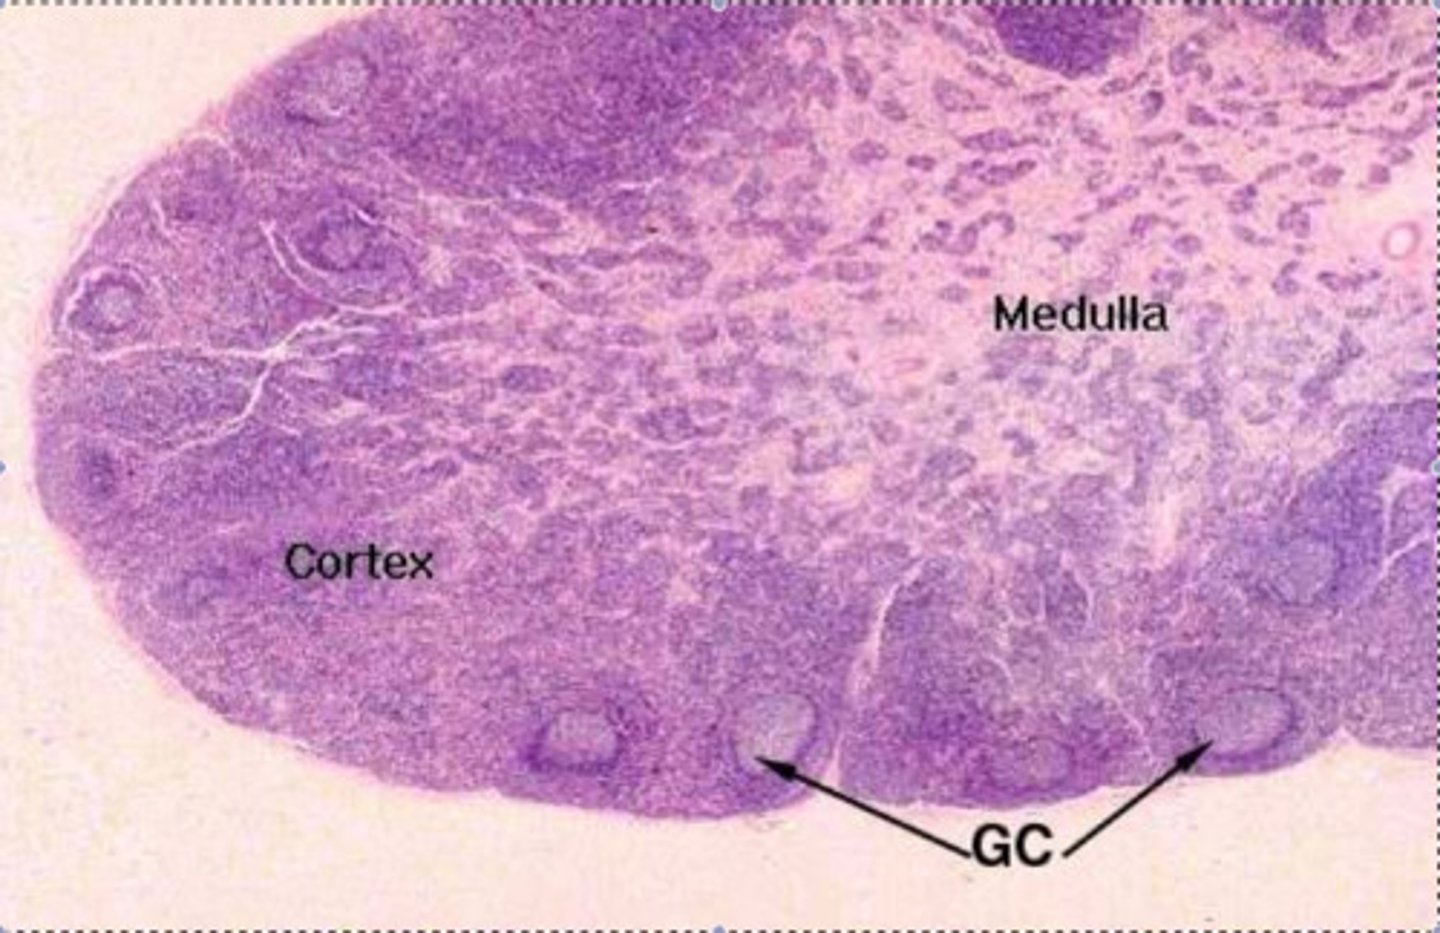

cortex (lymph node)

Contains clusters of lymphocytes. The outer region of a lymph node containing B cells, dendritic cells, and macrophages, playing a key role in immune response activation.

medulla (lymph node)

Medullary cords extend inward from cortex and contain B cells, T cells, and plasma cells

medullary cords (lymph node)

lymphatic tissue in the medulla of a lymph node filled with B cells, plasma cells, and macrophages, playing a role in antibody production and immune response.